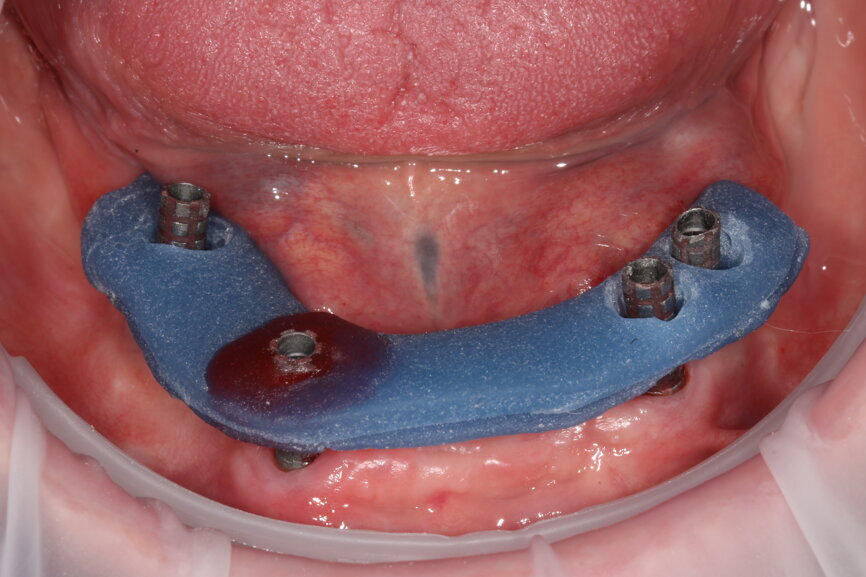

Fig. 15: Verification jig locked in situ to gain implant passivity.

With greater numbers of implants and fewer teeth to act as reference points, intra-oral scanning becomes less reliable—particularly across the arch—so we need to exercise caution and be aware of its limitations. We have used composite flow stuck to the soft tissue to increase reference points for our scanners, increasing their ability to stitch images more accurately together. With this in mind, we cannot assume the scan is accurate and any framework fabricated would be non-passive; therefore, we must use other methods to verify the scan’s accuracy. We have found locking temporary abutments within a composite framework intra-orally the easiest and most reproducible way to do this. It then allows us to design and mill a truly passive framework by Createch and a temporary acrylic bridge.